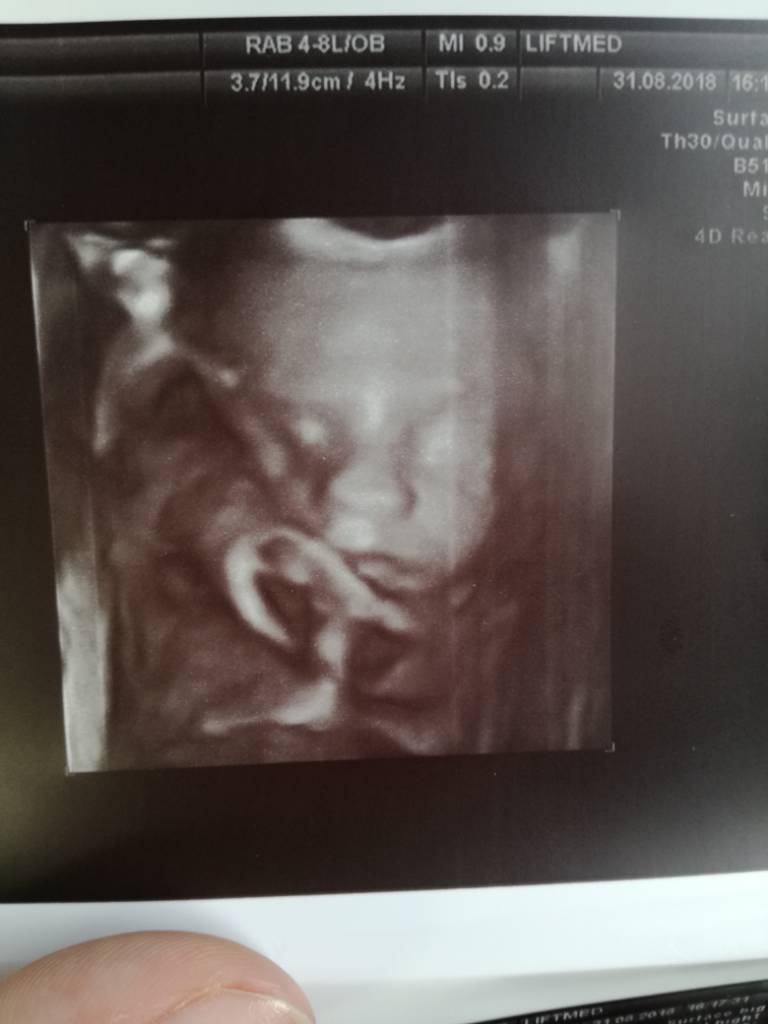

Narazie moge sie pochwalić takim :)

IMG_20180831_170855.jpg

@Dagaa11, cudne maleństwo [emoji173]️[emoji173]️[emoji173]️ z którego tygodnia to zdjęcie?

Dziekuję :* z dzisiaj, 26+2 :)